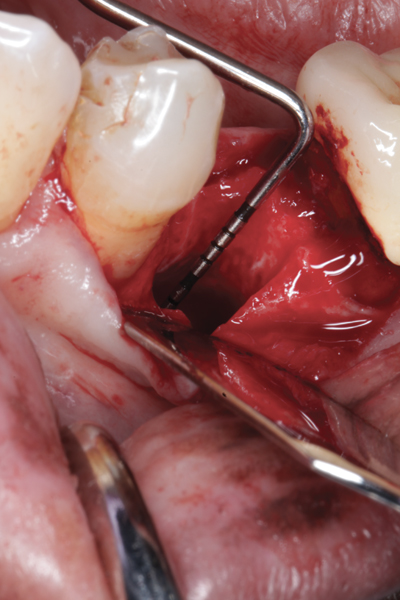

Fig 1. (Case 1) Tooth No. 19 manifested a buccal fistulous tract. Probing depth on the buccal was 8 mm.

Figure 1

Fig 2. Buccal flap elevated exposing buccal plate defect.

Figure 2